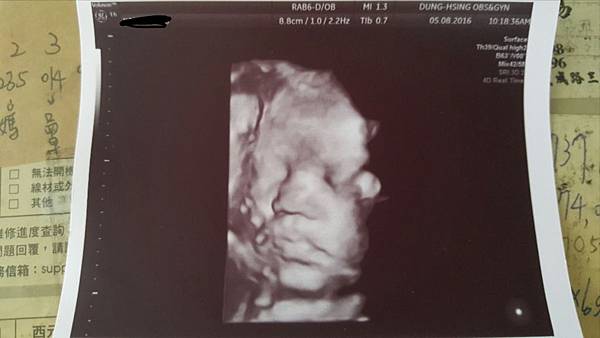

今天去照了4D超音波

主要是以嘗鮮為目的啦這機器跟高雄的產檢醫院滿類似的

順便看看寶寶到底長什麼樣子![]()

照片是她的腿骨測量右下角寫著重量1906g評估是32W.....還有點小隻表示我要繼續再吃養胎中藥

小妹妹的臉大鼻子厚唇跟萱萱剛出生時有點像

妹妹在笑